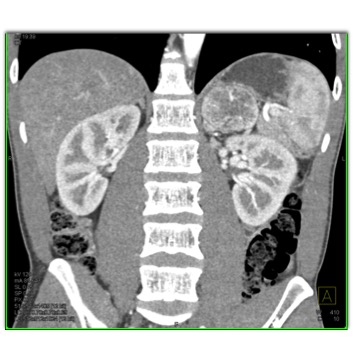

The most likely diagnosis in this case is?

adrenal lymphoma

pheochromocytoma

primary adrenal carcinoma

metastatic renal cell carcinoma